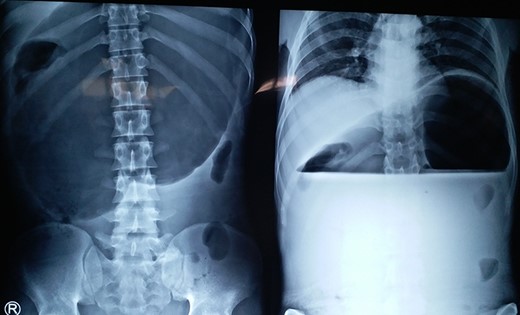

Chronic gastric volvulus, showing raised left hemi-diaphragm in chest X-ray, with intraoperative placement of double gastrostomy tube for fixation.

A 75-year-old male presented to the emergency with severe pain in the epigastrium, multiple episodes of non-bilious vomiting and epigastric fullness for the past 2 days. There was no history of weight loss, anorexia, hematemesis or early satiety. Eight months before, he had similar complain (resolved spontaneously), was admitted, and evaluated with upper GI endoscopy and CT abdomen, with normal findings. On examination, patient was tachycardic but normal blood pressure. There was epigastric fullness with mild tenderness. Blood investigations revealed normal hemoglobin, but leukocytosis (16 000 cells/mm3). The renal function test and serum chemistry were normal. Chest X-ray was done, which showed elevated left hemi-diaphragm with large gastric shadow beneath it (Fig. 3). In view of recurring symptoms, chronic gastric volvulus was considered as differentials. On further imaging with CT abdomen, it confirmed gastric volvulus. Patient was taken up for emergency laparotomy. Intraoperatively, organo-axial gastric volvulus secondary to diaphragmatic eventration was seen. It was de-rotated and fixation of the stomach was performed by double, non-draining tube gastrostomy (at two points, body and antrum) with sham gastrojejunostomy to prevent recurrence (Fig. 3). No attempt at the plication of eventration was done due to the technical difficulty, splenic capsular tear and secured stomach fixation. The patient did well postoperatively and was discharged on Day 8. At 38 months follow-up, the patient is asymptomatic.